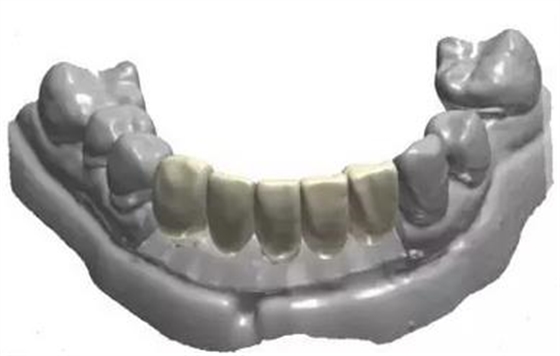

去除不良修復(fù)體后鄰牙松動

利用3shape導(dǎo)板軟件虛擬排牙